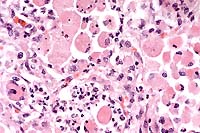

Case 24-2a. Lung. Condensed basophilic nuclear inclusion (adenovirus) in a necrotic alveolar epithelial cell. This alveolus and others have sloughing necrotic, hypereosinophilic pneumcytes with a moderate influx of neutrophils and fibrin.

Case 24-2b. Pancreas. Sloughing pancreatic duct epithelial cells with condensed basophilic nuclear inclusions with intralumenal debris and neutrophils (left). . A few residual cells of the degenerating exocrine pancreas still have faint granular, eosinophilic zymogen granules (right). 40X

AFIP Diagnoses:

1. Lung: Pneumonia, interstitial, acute, diffuse, moderate, with multifocal intraepithelial eosinophilic intranuclear inclusion bodies, Arabian horse, equine.

2. Lung: Pneumonia, pyogranulomatous, multifocal, random, moderate.

3. Pancreas, exocrine: Degeneration, necrosis, and loss, multifocal, moderate, with regeneration, fibrosis, ductular necrosis and acute inflammation, and intraepithelial eosinophilic intranuclear inclusion bodies.

Conference Note: Gram stains performed at the AFIP revealed moderate numbers of intrahistiocytic gram positive coccobacilli within pulmonary granulomas.